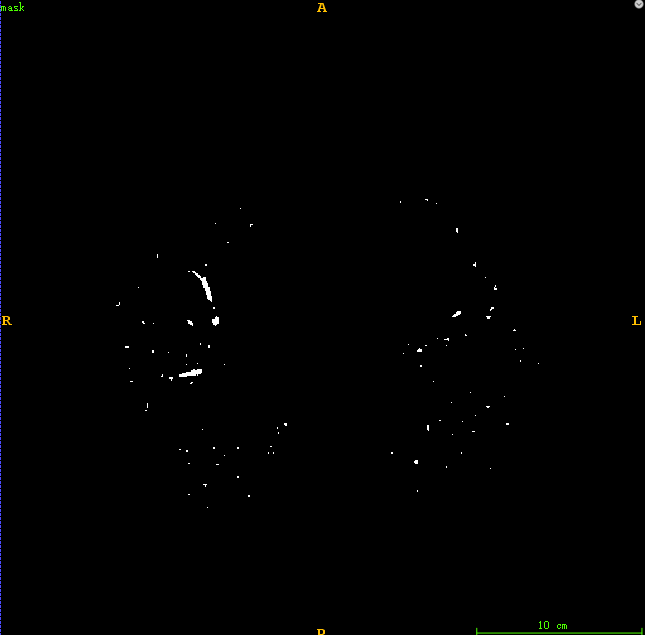

最后得到肺部区域图像如下所示。

通过对比度增强处理后得到的血管区域呈现出明显的明亮特征,在后续处理中我们采用了一种基于阈值的二值化方法对增强后的图像进行分割。具体而言,在完成上述操作后生成的结果中仅保留了具有显著特征的血管区域轮廓。这一过程能够有效地区分出不同类型的血管结构。